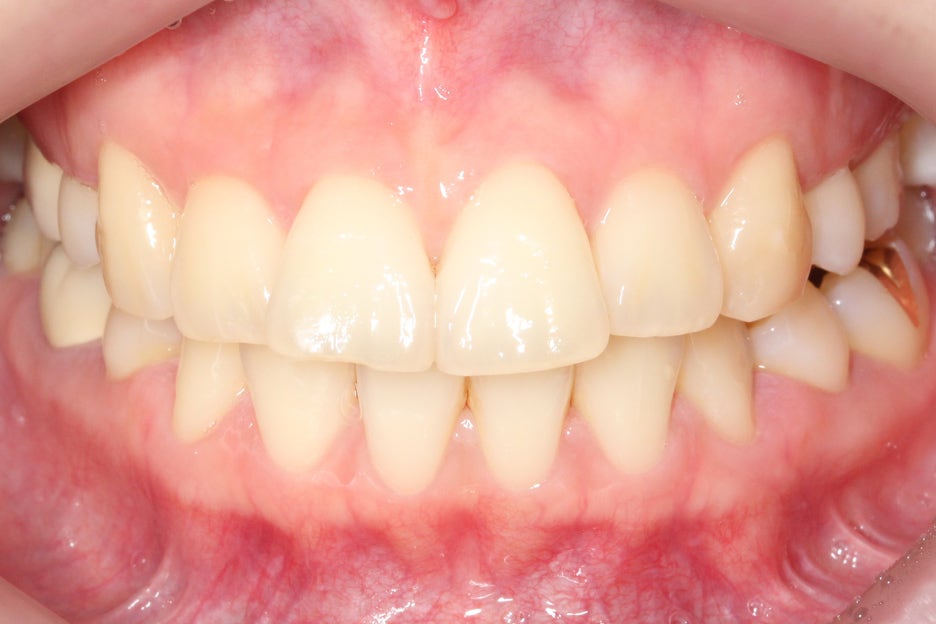

상악 클리피씨 교정 case

위의 case는 토끼앞니교정을

진행하기 전 정밀진단 상황으로

상악 중절치의 돌출감이

심한 모습인데요,

특히 upper teeth와

lower teeth의 정중선이

어긋나 있기 때문에

전치부의 crowding이

더 강조되는 상황입니다.